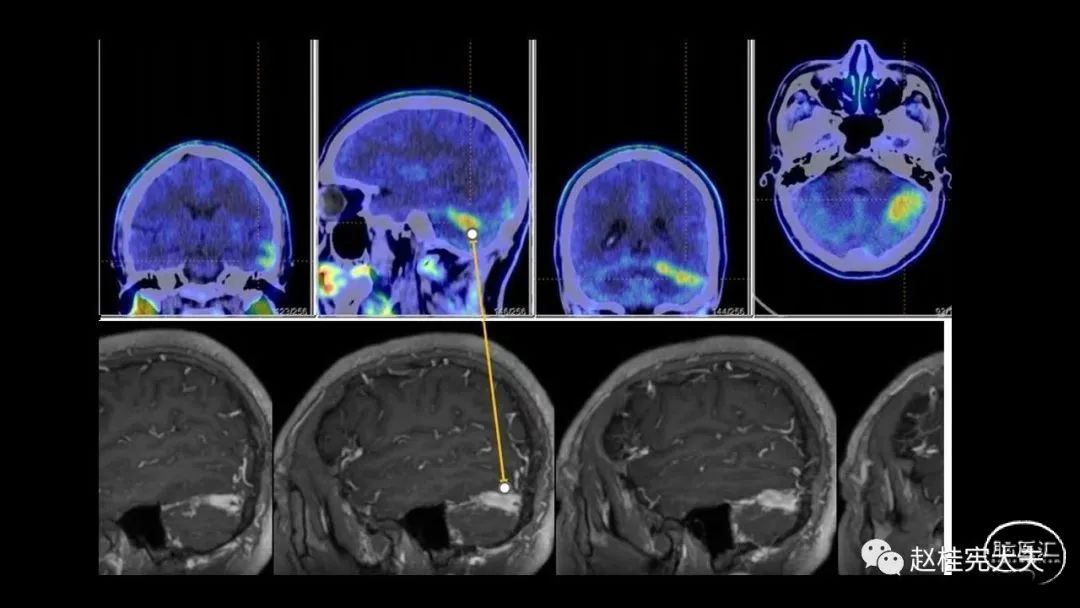

术前例行提交脑胶质瘤MDT讨论本病例,本例患者影像资料如下:

重点分析患者影像资料:

进一步完善头颅CTA、颅脑磁共振SWI及颅脑MRV,见以下图片: